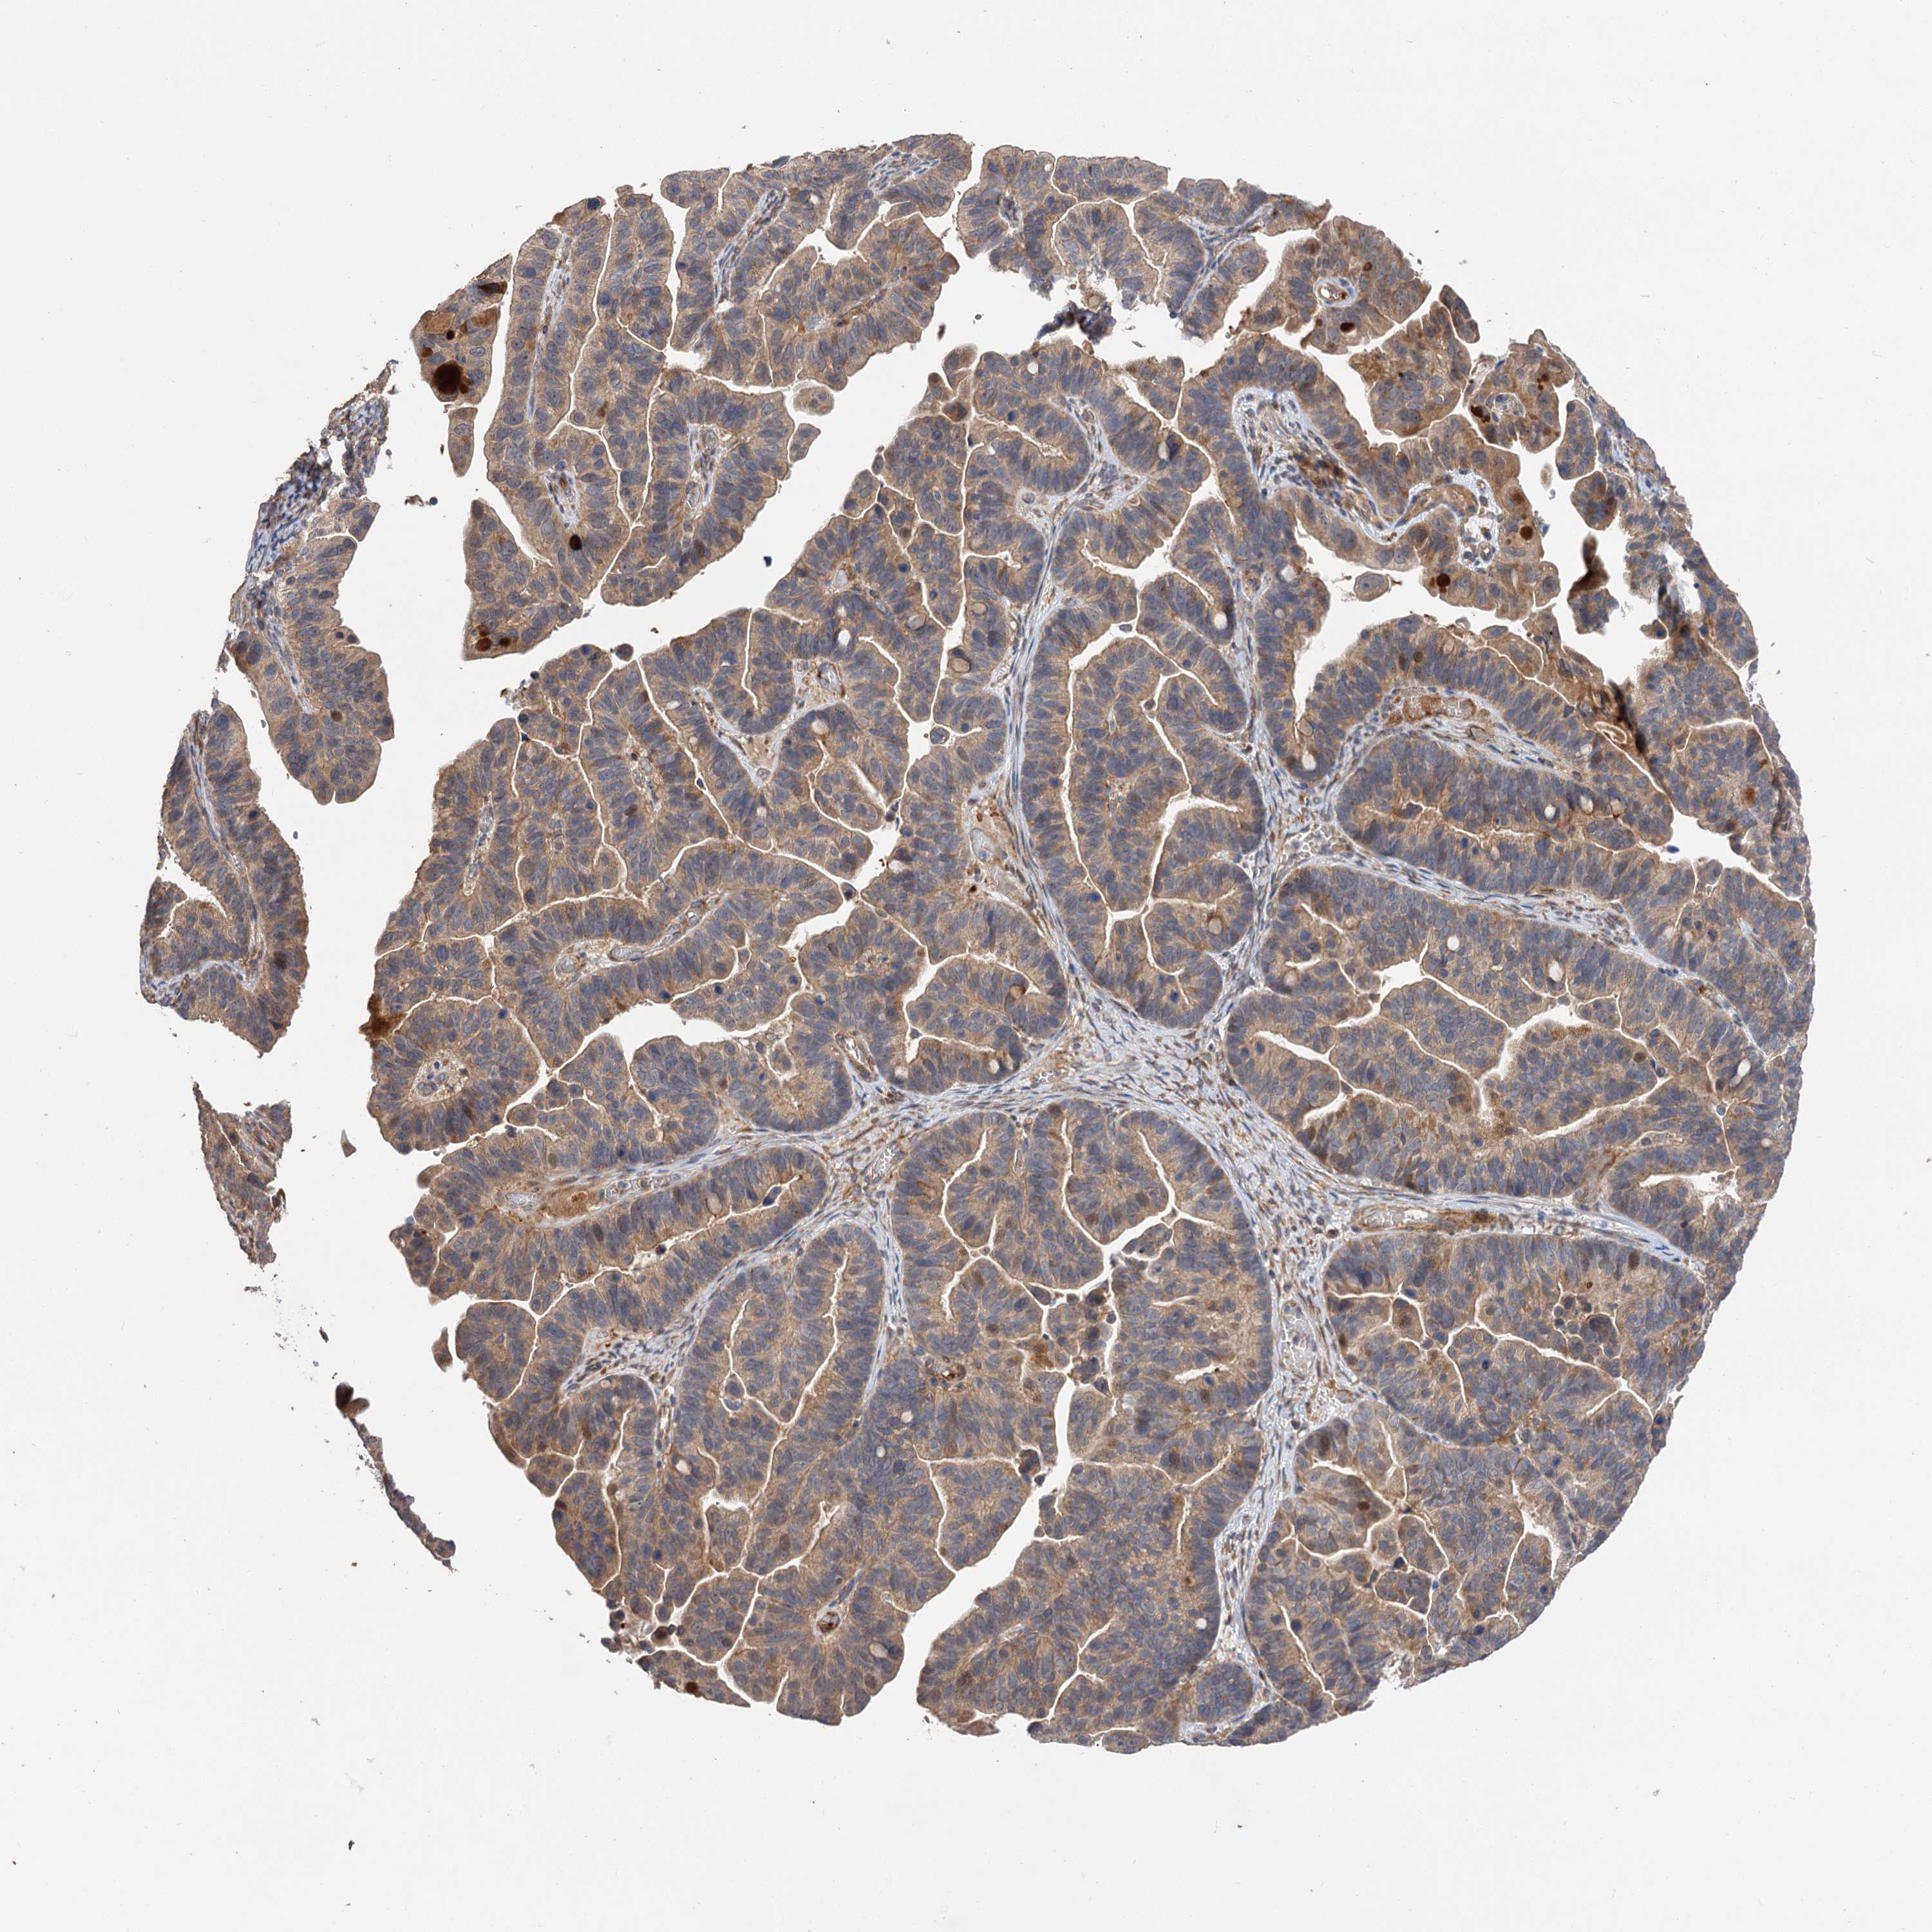

OVARIAN CANCER - Protein expressioni

A mouse-over function shows sample information and annotation data. Click on an image to view it in a full screen mode. Samples can be filtered based on level of antibody staining by selecting one or several of the following categories: high, medium, low and not detected. The assay and annotation is described here.

Note that samples used for immunohistochemistry by the Human Protein Atlas do not correspond to samples in the TCGA dataset.

Antibody stainingi

Antibody staining in the annotated cell types in the current human tissue is reported as not detected, low, medium, or high, based on conventional immunohistochemistry profiling in selected tissues. This score is based on the combination of the staining intensity and fraction of stained cells.

Each image is clickable and will lead to virtual microscopy that enables deeper exploration of all samples and also displays staining intensity scores, fraction scores and subcellular localization as well as patient and tissue information for each sample.

Antibody HPA038850

Antibody HPA038851

Cystadenocarcinoma, serous, NOS

Carcinoma, endometroid

Cystadenocarcinoma, mucinous, NOS

Carcinoma, NOS